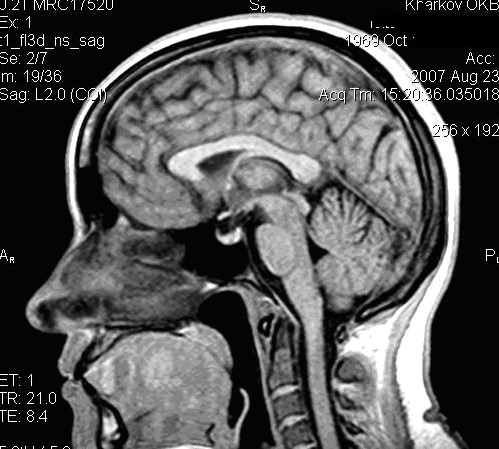

При изучении структур мозги МРТ имеет некоторые преимущества перед КТВо-первых, на MP-томограммах более четко различаются структурные элементы головного мозга, отчетливее дифференцируются белое и серое вещество, все стволовые структуры. На качестве магнитно-резонансных то­мограмм не отражается экранирующее действие костей черепа, ухудшаю­щее качество изображения при КТ. Во-вторых, МРТ можно производить в разных проекциях и получать не только аксиальные, как при КТ, но и фронтальные, сагиттальные и косые слои. В-третьих, это исследование не связано с лучевой нагрузкой. Особым достоинством МРТ является возмож­ность отображения сосудов, в частности сосудов шеи и основания головно­го мозга, а при контрастировании гадолинием -- и мелких сосудистых вет­вей (см. рис. 35 и 36).

Рис. 35.         МРТ изображения  области головы в сагиттальной и фронтальной плоскостях Т1 ВИ,  хорошо различимы структуры головного мозга.